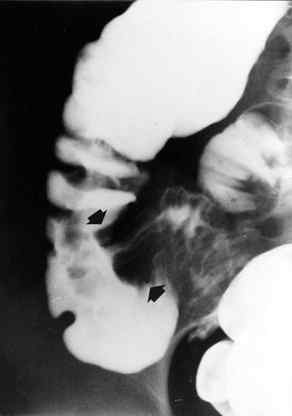

“Utero e ovaie nei limiti d’età. In fossa iliaca dx si evidenzia, in sede di ultima ansa ileale e valvola ileo-ciecale, massa con aspetto “a bersaglio” di 3x2 cm compatibile con invaginazione ileo-ciecale. Presente in prossimità formazione linfonodale ingrandita del diametro massimo di 1,5 cm. L’appendice ciecale appare un po’ ingrossata (diametro trasverso di 8 mm) con ecostruttura della parete conservata” (Figura 1 e 2).

Dopo aver allertato la Sala Operatoria, eseguiva clisma opaco (che conferma la diagnosi) (Figura 3), per tentare la riduzione dell’invaginazione, manovra che purtroppo non riesce. Alle ore 12 viene operata, con riduzione del segmento invaginato, associato ad appendicectomia. È dimessa in 6° giornata perfettamente guarita.

L’aspetto ecografico dell’invaginazione è molto caratteristico per la presenza di anelli concentrici o “a bersaglio” in scansione trasversale. L’invaginante è ipoecogeno, a causa dell’edema parietale, mentre l’invaginato è iperecogeno, in quanto contiene i foglietti mucosi e il contenuto intestinale, liquido o gassoso, intrappolato tra questi (5).